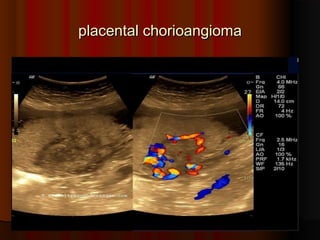

placental chorioangiomaplacental chorioangioma Sonography of the placenta inSonography of the placenta in this 16 week pregnancy showsthis 16 week pregnancy shows a large, solid mass, that is nona large, solid mass, that is non calcific and shows mildcalcific and shows mild vascularity (vascular) andvascularity (vascular) and excludes placental hematomaexcludes placental hematoma.. and shows many cystic spacesand shows many cystic spaces within itwithin it.. This tumor of theThis tumor of the placenta lies close to the cordplacenta lies close to the cord insertion siteinsertion site.. UltrasoundUltrasound images of this type of placentalimages of this type of placental mass are highly suggestive ofmass are highly suggestive of placental chorioangiomaplacental chorioangioma..